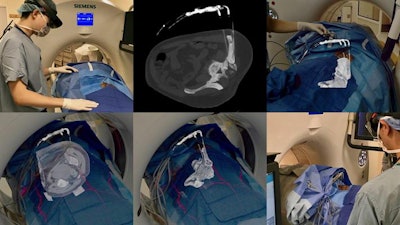

- Percutaneous procedures: An increasing number of groups have developed techniques using AR to navigate percutaneous needle-based procedures. Proof-of-concept studies have demonstrated that relying on AR holograms to guide percutaneous bone interventions, liver biopsies, and similar procedures can reduce radiation dose, procedure times, and the number of images acquired.

Other studies have shown that AR can facilitate optimal probe placement for ablation procedures, lower targeting errors for needle tracking, and improve resource utilization during needle localization. In one study, researchers used AR technology to guide needle insertion into lumbar spine phantoms with high accuracy based on preoperative CT data, eliminating the need for real-time CT fluoroscopy.